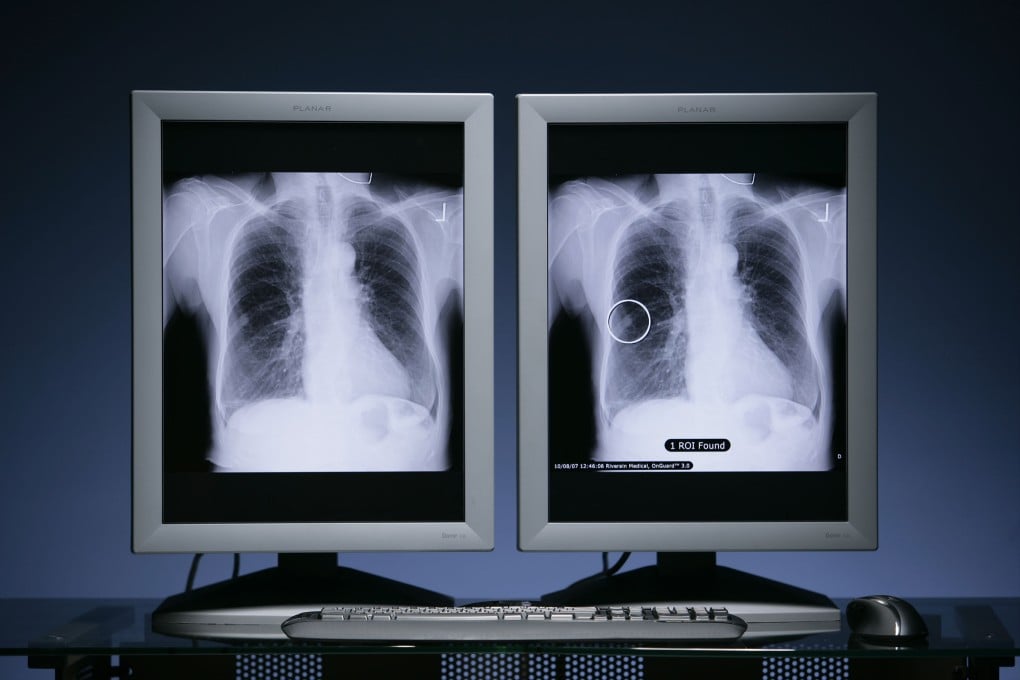

Kanker paru-paru dengan mutasi HER2 sangat sulit diobati dan saat ini hanya memiliki satu jenis obat yang disetujui oleh FDA, yaitu terapi antibody-drug conjugate atau ADC. Terapi ini diberikan secara intravena dan sering menyebabkan efek samping seperti diare, mual, kelelahan, dan ruam pada kulit.

Obat baru zongertinib adalah obat oral yang dapat diminum dan bekerja dengan menargetkan protein HER2 yang menjadi penyebab pertumbuhan kanker. Berbeda dari terapi sebelumnya, zongertinib menunjukkan hasil yang lebih baik dan risiko efek samping yang lebih rendah.